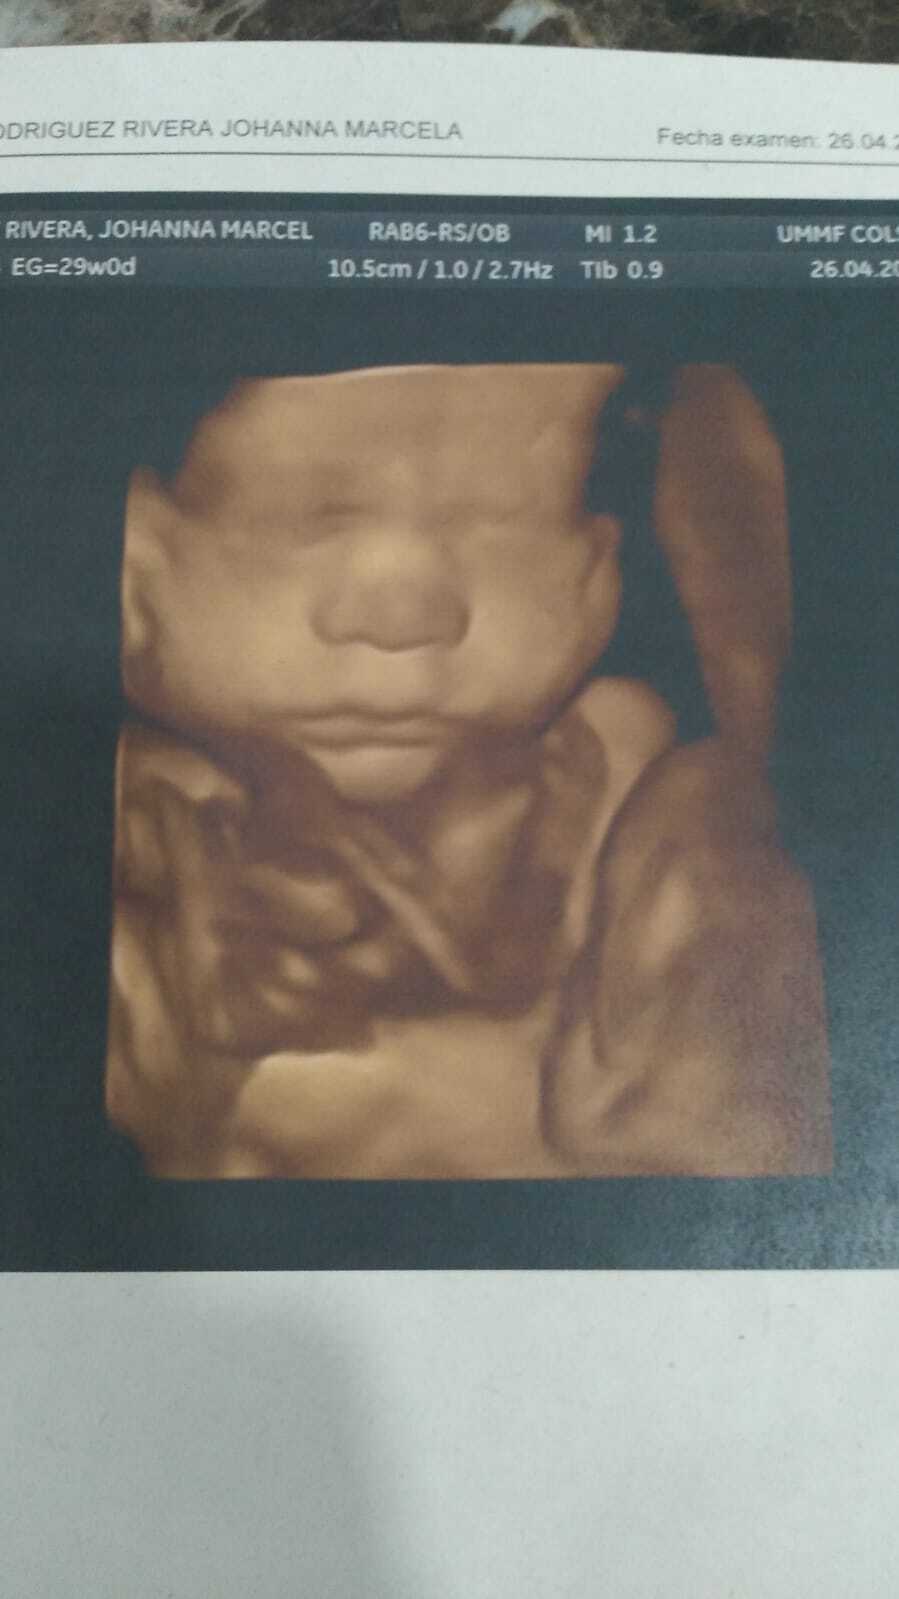

ULTRASON